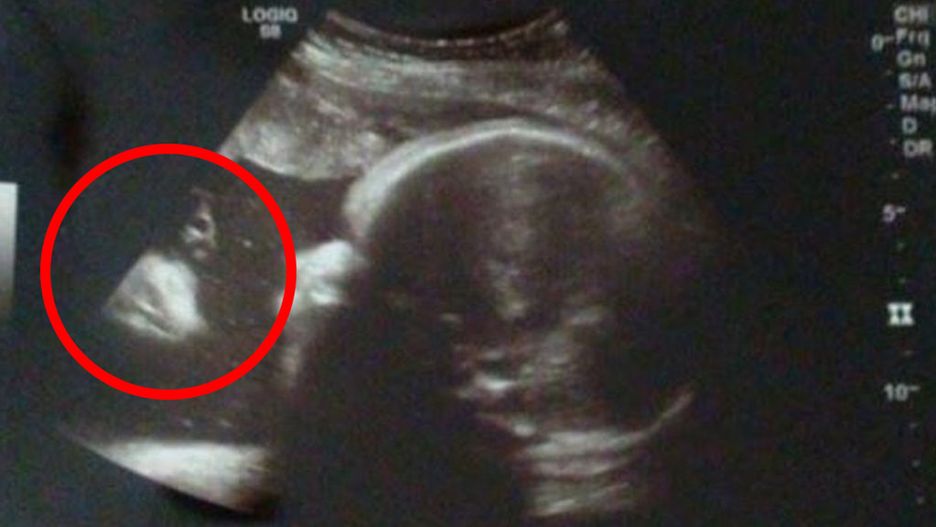

Para zobaczyła na USG dziecka… Jezusa

Na zdjęciu USG brzucha mamy rodzice dziecka dopatrzyli się brodatej twarzy przypominającej Jezusa.

Para z Pensylwanii była mocno zaskoczona. Na początku nie mogli uwierzyć, że na zdjęciu widać jakąś postać. Przecierali oczy ze zdumienia, ale wciąż widzieli czyjąś podobiznę tuż obok główki ich córki. Charakterystyczny kształt postaci od razu przywołał im na myśl Jezusa.

Kiedy to zobaczyłam, o mało się nie popłakałam. Odebrało mi mowę. Po prostu nie mogłam uwierzyć w to, co zobaczyłam – mówi mama Alicia Zeek w rozmowie z fox43.com.

Zarówno Alicia jak i jej mąż Zac mówią o sobie, że nie są zbyt religijni. Kształt twarzy uchwyconej na zdjęciu nie pozostawia ich zdaniem dużego pola do domysłu. Tak samo twierdzą internauci, którzy komentowali zdjęcie na Facebooku.

Para twierdzi, że to był znak. Córka Briella urodziła się zdrowa. Rodzice obawiali się problemów, ponieważ te pojawiły się w przypadku jej rodzeństwa. Pierwsza córka Alicii i Zaca urodziła się z dwoma kciukami na jednej dłoni. Syn natomiast miał rozszczepienie wargi i podniebienia. Do tego istniało duże ryzyko, że on i jego mama umrą w czasie porodu.

To, że ludzie widzą na tym zdjęciu twarz wcale nie jest dziwne. Takie zjawisko nazywa się pareidolią. Polega ono na dopatrywaniu się znanych kształtów w przypadkowych szczegółach. Dlatego też np. niektóre kratery na Marsie przypominają twarze lub chmury układają się w kształt serca czy smoka.